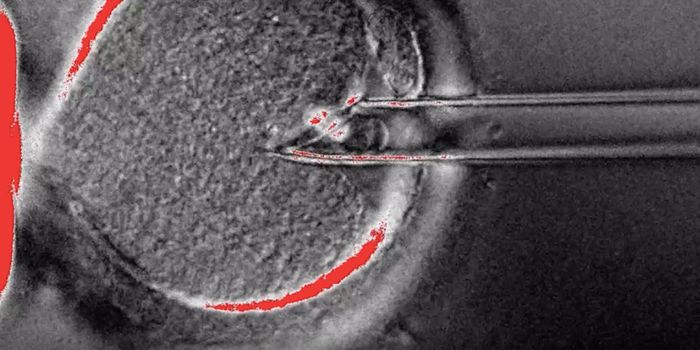

SEP 24, 2021Cell & Molecular BiologyThis photo by Sozen & Jorgensen et al., Nature Communications, shows an embryo-like structure made from human stem cells ...

MAY 11, 2021Cell & Molecular BiologyThis ©MPI for Biophysical Chemistry microscopy image shows a bovine egg after fertilization.